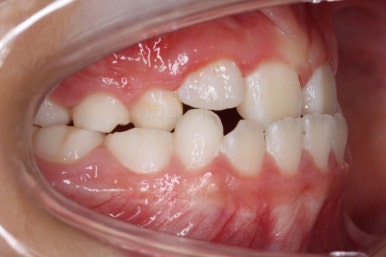

전후 비교를 해볼게요.

부산소아교정 키다리아저씨치과에서 치료를 한 이번 사례를 비교해 보면 왼쪽이 치료 전, 오른쪽이 치료 후 사진입니다.

이렇게 비교해 보니 변화가 더 눈에 띄실거에요.